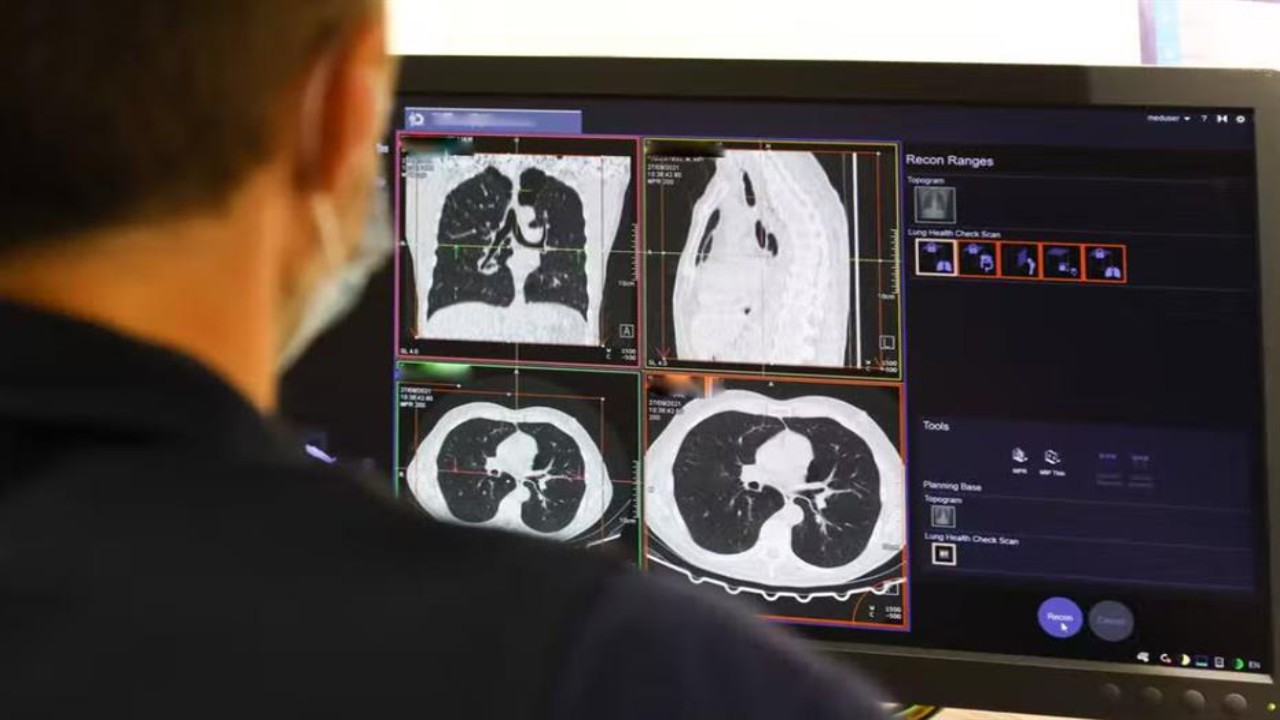

التهاب رئوي

3 مضاعفات خطيرة قد تحدث عند إصابتك بالالتهاب الرئوي .. فيديو

اكتظاظ مستشفيات الصين بالأطفال المصابين بالعدوى المختلطة.. فيديو

منذ 3 سنة

2

4857